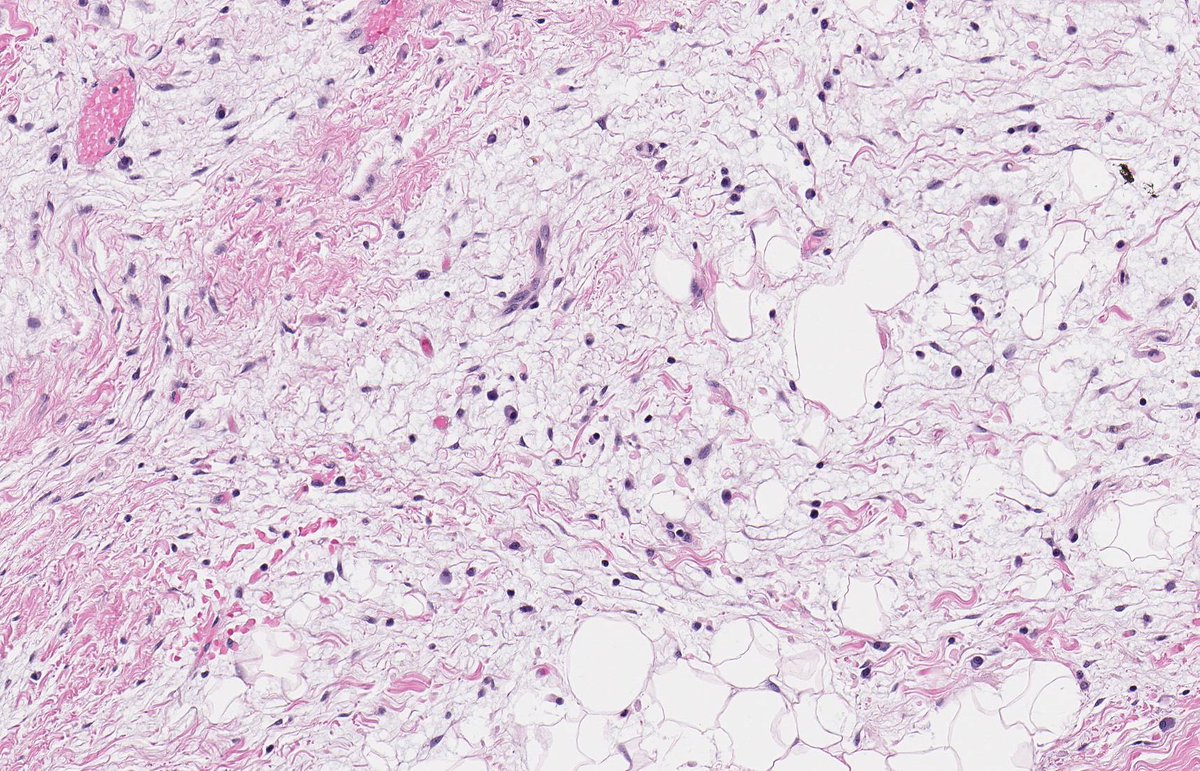

PERINEPHRIC MYXOID PSEUDOTUMOUR OF FAT. NB: sheets of mature adipocytes; spindle-stellate cells in myxoid stroma; mild chronic inflammatory infiltrate; MDM2 non-amp; may arise in context of renal cell disease and transplantation (PMID: 19525929, 30826321, 33835530).